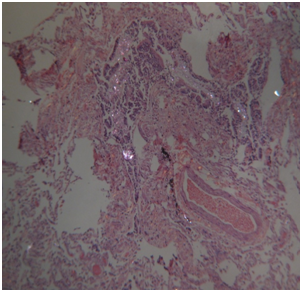

Histology: Acute emphysema was the prominent observation; edema and hemorrhages were also present.4 In 9 cases (Figures 3-6), exogenous material in the airways, comprehensive of planktonic boli in the lower branches, clearly demonstrable at polarization microscope (and possibly confirmable at SEM’s elemental analysis with EXD). Zoo- and phytoplankton have been better identified in the UV microscope. It is mandatory to differentiate the planktonic material from gastric content, regurgitated and aspirated (Figure 7 & 8).

Figure 6 Drowning in freshwater; recovery corpse after few hours. Geo- and phytoplankton in a lower bronchus (EE, 120X, polarized light).